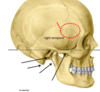

petrous part of temporal bone

zygomatic process of temporal bone

arises from squamous part and articulates wihth zygomatic bone

pterion

frontal, parietal, temporal and sphenoid bones

thinnest part of the skull

which part of the temporal bone is the mastoid process found on

petrous part